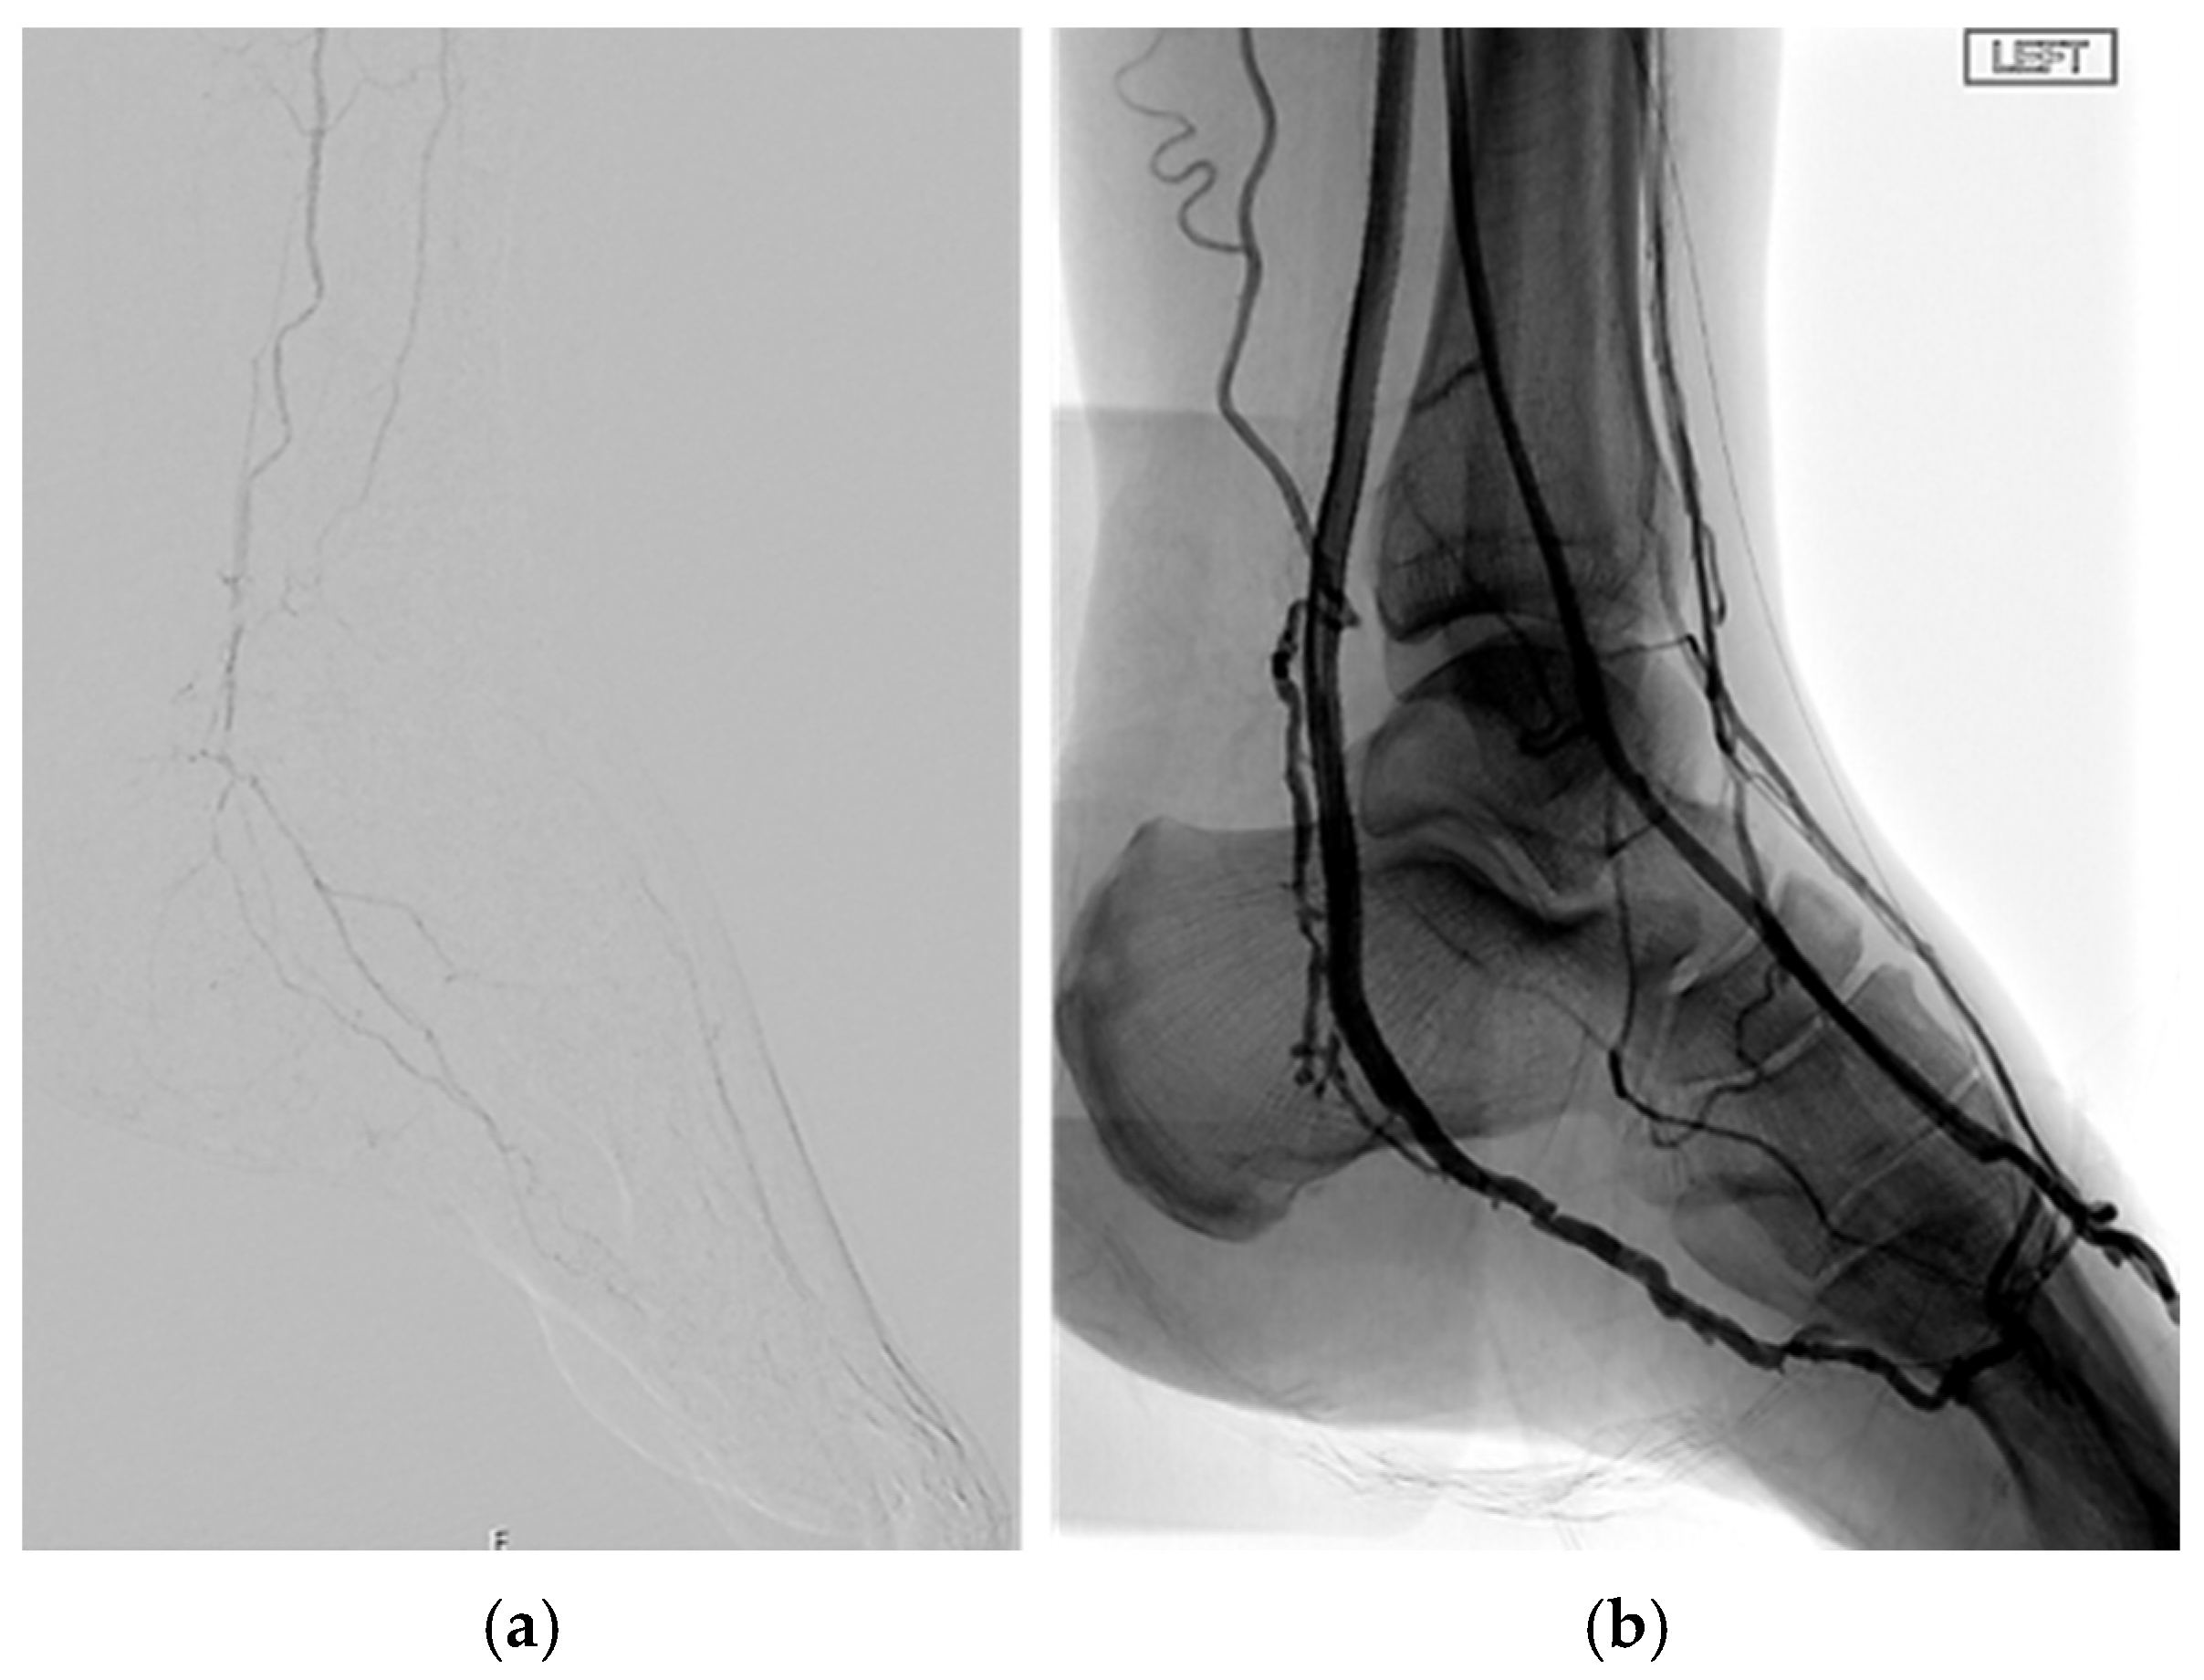

- Ferraresi, R.; Mauri, G.; Losurdo, F.; Troisi, N.; Brancaccio, D.; Caravaggi, C.; Neri, L. BAD transmission and SAD distribution: A new scenario for critical limb ischemia. J. Cardiovasc. Surg. 2018, 59, 655–664. [Google Scholar] [CrossRef] [PubMed]

- Ferraresi, R.; Ucci, A.; Pizzuto, A.; Losurdo, F.; Caminiti, M.; Minnella, D.; Casini, A.; Clerici, G.; Montero-Baker, M.; Mills, J. A Novel Scoring System for Small Artery Disease and Medial Arterial Calcification Is Strongly Associated with Major Adverse Limb Events in Patients with Chronic Limb-Threatening Ischemia. J. Endovasc. Ther. 2021, 28, 194–207. [Google Scholar] [CrossRef] [PubMed]

- Meloni, M.; Izzo, V.; Da Ros, V.; Morosetti, D.; Stefanini, M.; Brocco, E.; Giurato, L.; Gandini, R.; Uccioli, L. Characteristics and Outcome for Persons with Diabetic Foot Ulcer and No-Option Critical Limb Ischemia. J. Clin. Med. 2020, 9, 3745. [Google Scholar] [CrossRef] [PubMed] [PubMed Central]